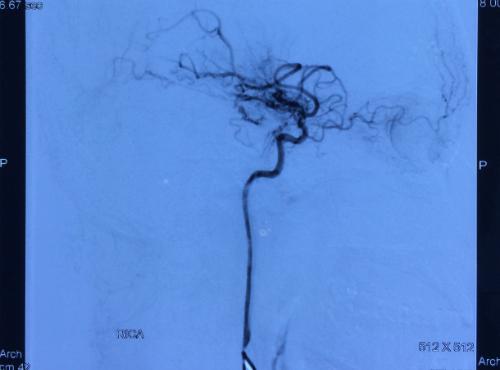

Nếu yếu tố nguy cơ quan trọng nhất ở đột quỵ người lớn là do các mảng xơ vữa thì ở đột quỵ trẻ em có 3 nhóm nguyên nhân hay gặp nhất là: bệnh tim bẩm sinh, bệnh Moya Moya (một loại bệnh lý tắc hẹp mạch não bẩm sinh) và bóc tách động mạch.

Hình ảnh mạch máu của trẻ bị bệnh Moya Moya - một loại bệnh lý tắc hẹp mạch não bẩm sinh

Hình ảnh mạch máu của trẻ bị bệnh Moya Moya – một loại bệnh lý tắc hẹp mạch não bẩm sinh